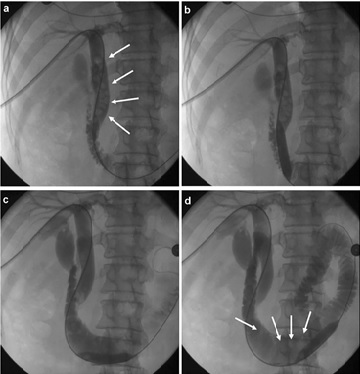

증상이 있거나 크기가 큰 경우, 증상이 없는 경우 담석증 치료법의 진행은 필요 없습니다. 일부 작은 담석은 스스로 몸을 통과할 수도 있습니다. 그런데 담석의 크기가 3cm 이상이고 도자기 형태로 비정상적인 벽의 비후 그리고 비정상적인 담낭의 기능 저하, 담낭 용종이 동반되는 경우라고 할 수 있습니다. 이런 증상이 있음에도 불구하고 방치하게 되면 천공이나 패혈증 같은 중대한 합병증이 많이 발생할 수 있기 때문에 통증이 나타나면 바로 해결해야 합니다.

대부분 담석증 치료법 중에서 담낭을 절제해서 우리 몸에 큰 변화가 올 거라고 생각합니다. 하지만 돌만 제거하는 것은 재발의 위험성이 있고 남아 있는 주요 총담관구조가 담낭의 기능을 대체하게 되므로 후유증은 크게 걱정하지 않으셔도 됩니다.

흉터가 거의 보이지 않기 때문에 저희 병원은 담석증 치료법은 단일 통로 복강경으로 복부에 큰 흉터를 남기는 개복술이 아닌 최소 침습으로 시행하기에 빠른 시간 내에 회복이 가능한 것이 특징입니다. 무엇보다 배꼽에 1.5cm 정도의 절개로 진행되고 있기 때문에 그 후 상처의 걱정은 없습니다. 뿐만 아니라 30분 내외로 모두 마무리되어 일반적인 일상생활로 빠르게 복귀할 수 있습니다.